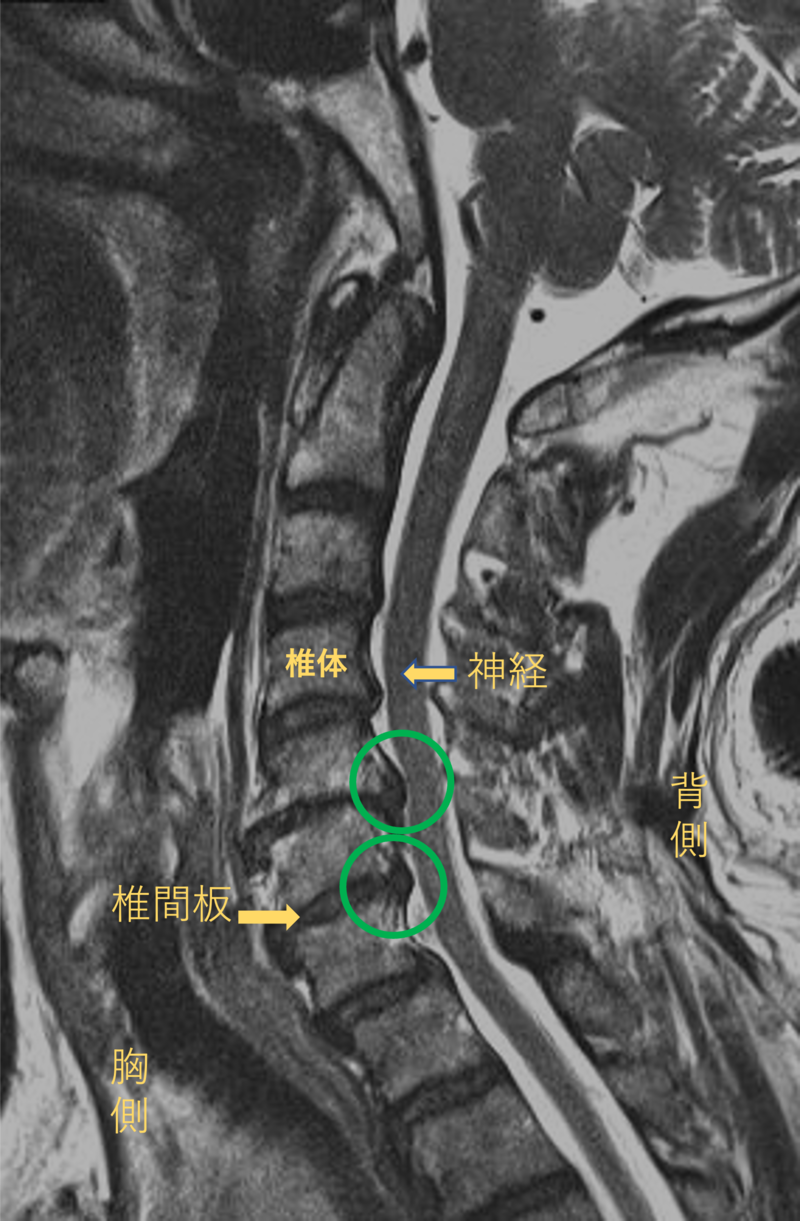

首を横から見たMRI画像です。

頚椎という骨と骨の間に椎間板と呼ばれるクッションがあります。

このクッションの中身が飛び出す状態が椎間板ヘルニアと呼ばれます。

このMRI画像では、椎間板が背中側に飛び出して神経が圧迫されることが痛み、しびれの原因となっておりました。